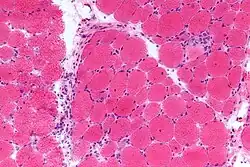

Die Diagnose wird anhand der oben beschriebenen klinischen Merkmale gestellt. Zusätzlich beweisend für DM sind erhöhte Muskelenzyme (Creatinkinase), Transaminasen und LDH. Eine Muskelbiopsie ist nur in Ausnahmefällen notwendig. Im Elektromyogramm lässt sich oft eine Myositis nachweisen.

Differentialdiagnostisch müssen vor allem ein Lupus erythematodes, eine Polymyositis und eine Leishmaniose ausgeschlossen werden. Auch Demodikosen, Dermatophytosen, Pyodermien und ischämische Vaskulopathien können ähnliche Symptome verursachen. Die Diagnose kann über eine histologische Untersuchung eines Bioptats und eine Elektromyographie gesichert werden.